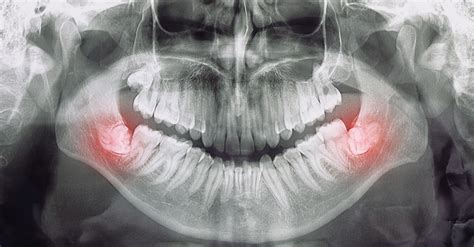

La extracción del cordal inferior derecho presenta riesgos particulares debido a su proximidad al nervio dentario inferior y al nervio lingual. Estos nervios son responsables de la sensibilidad en el labio inferior, el mentón, la lengua y las encías.

Factores de Riesgo para Lesiones Nerviosas

El factor de riesgo más asociado a la parestesia es la posición anatómica de la muela del juicio y su relación con el nervio. Una posición profunda o cercana al nervio aumenta el riesgo de lesión durante la extracción.

- Planificación preoperatoria: Realizar una evaluación exhaustiva de la posición de la muela del juicio y su relación con el nervio mediante radiografías y tomografías computarizadas (TAC).